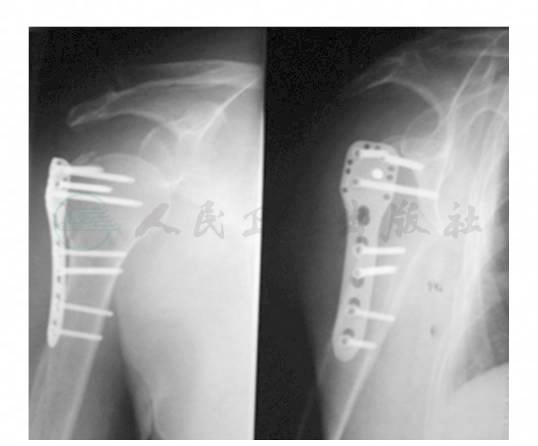

术后无需辅助外固定。术后第2日移除引流管,行X线检查示骨折复位满意,内植物位置良好(图2)。随即开始肩关节被动功能锻炼,包括钟摆样运动以及被动前屈、外旋锻炼。而后逐渐增加被动内旋、内收及外展练习。术后6~8周时复查X线片见骨折线模糊即开始主动功能锻炼,逐渐增强前屈、旋转及内收锻炼。术后12周开始各个方向上的抗阻力功能锻炼。

图2 术后第2天肩关节正侧位X线片